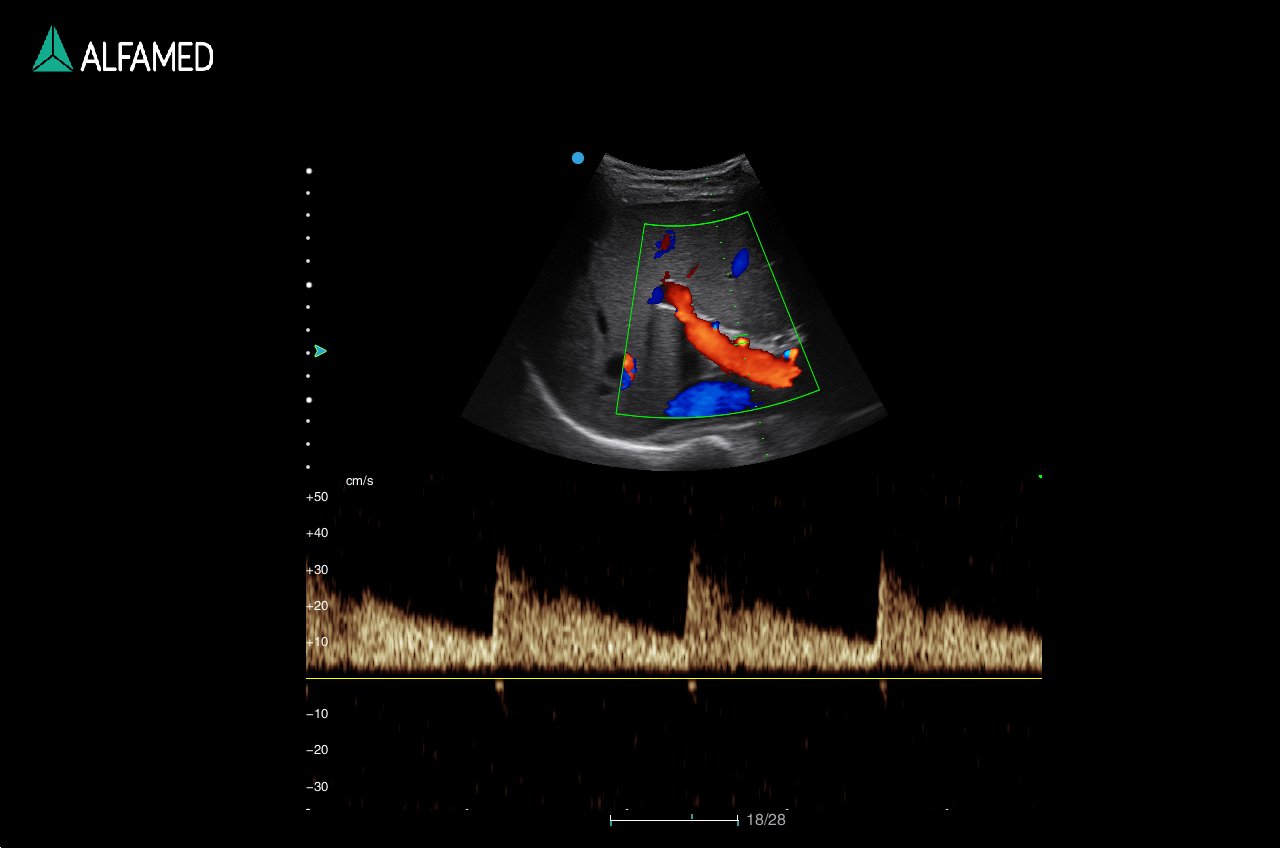

Dotado de softwares avançados e transdutores específicos, o Magnus X5 apresenta alta versatilidade para imagem geral e excelente performance, principalmente, nos exames de cardiologia avançada e obstetrícia.

- Panoscope com Color

- TDI

- CW

- VS Flow